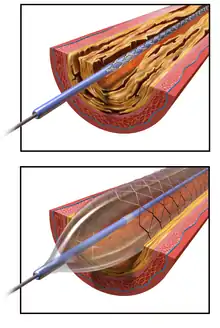

Angioplasty, also known as balloon angioplasty and percutaneous transluminal angioplasty (PTA), is a minimally invasive endovascular procedure used to widen narrowed or obstructed arteries or veins, typically to treat arterial atherosclerosis.[1] A deflated balloon attached to a catheter (a balloon catheter) is passed over a guide-wire into the narrowed vessel and then inflated to a fixed size.[1] The balloon forces expansion of the blood vessel and the surrounding muscular wall, allowing an improved blood flow.[1] A stent may be inserted at the time of ballooning to ensure the vessel remains open, and the balloon is then deflated and withdrawn.[2] Angioplasty has come to include all manner of vascular interventions that are typically performed percutaneously.

Access to the vascular system is typically gained percutaneously (through the skin, without a large surgical incision). An introducer sheath is inserted into the blood vessel via the Seldinger technique.[17] Fluoroscopic guidance uses magnetic resonance or X-ray fluoroscopy and radiopaque contrast dye to guide angled wires and catheters to the region of the body to be treated in real time.[18] Tapered guidewire is chosen for small occlusion, followed by intermediate type guidewires for tortuous arteries and difficulty passing through extremely narrow channels, and stiff wires for hard, dense, and blunt occlusions.[19] To treat a narrowing in a blood vessel, a wire is passed through the stenosis in the vessel and a balloon on a catheter is passed over the wire and into the desired position.[20] The positioning is verified by fluoroscopy and the balloon is inflated using water mixed with contrast dye to 75 to 500 times normal blood pressure (6 to 20 atmospheres), with most coronary angioplasties requiring less than 10 atmospheres.[21] A stent may or may not also be placed.

The initial form of angioplasty was 'plain old balloon angioplasty' (POBA) without stenting, until the invention of bare metal stenting in the mid-1980s to prevent the abrupt closure sometimes seen with POBA.[1]

Bare metal stents were found to cause in-stent restenosis as a result of neointimal hyperplasia and stent thrombosis, which led to the invention of drug-eluting stents with anti-proliferative drugs to combat in-stent restenosis.[1]